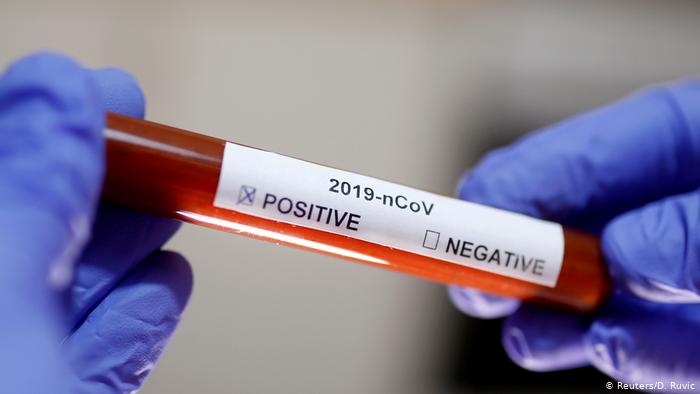

Según la OMS, el coronavirus pone en peligro los logros en la lucha contra la tuberculosis

The Lancet: impacto de COVID-19 puede elevar muertes por VIH, tuberculosis y malaria